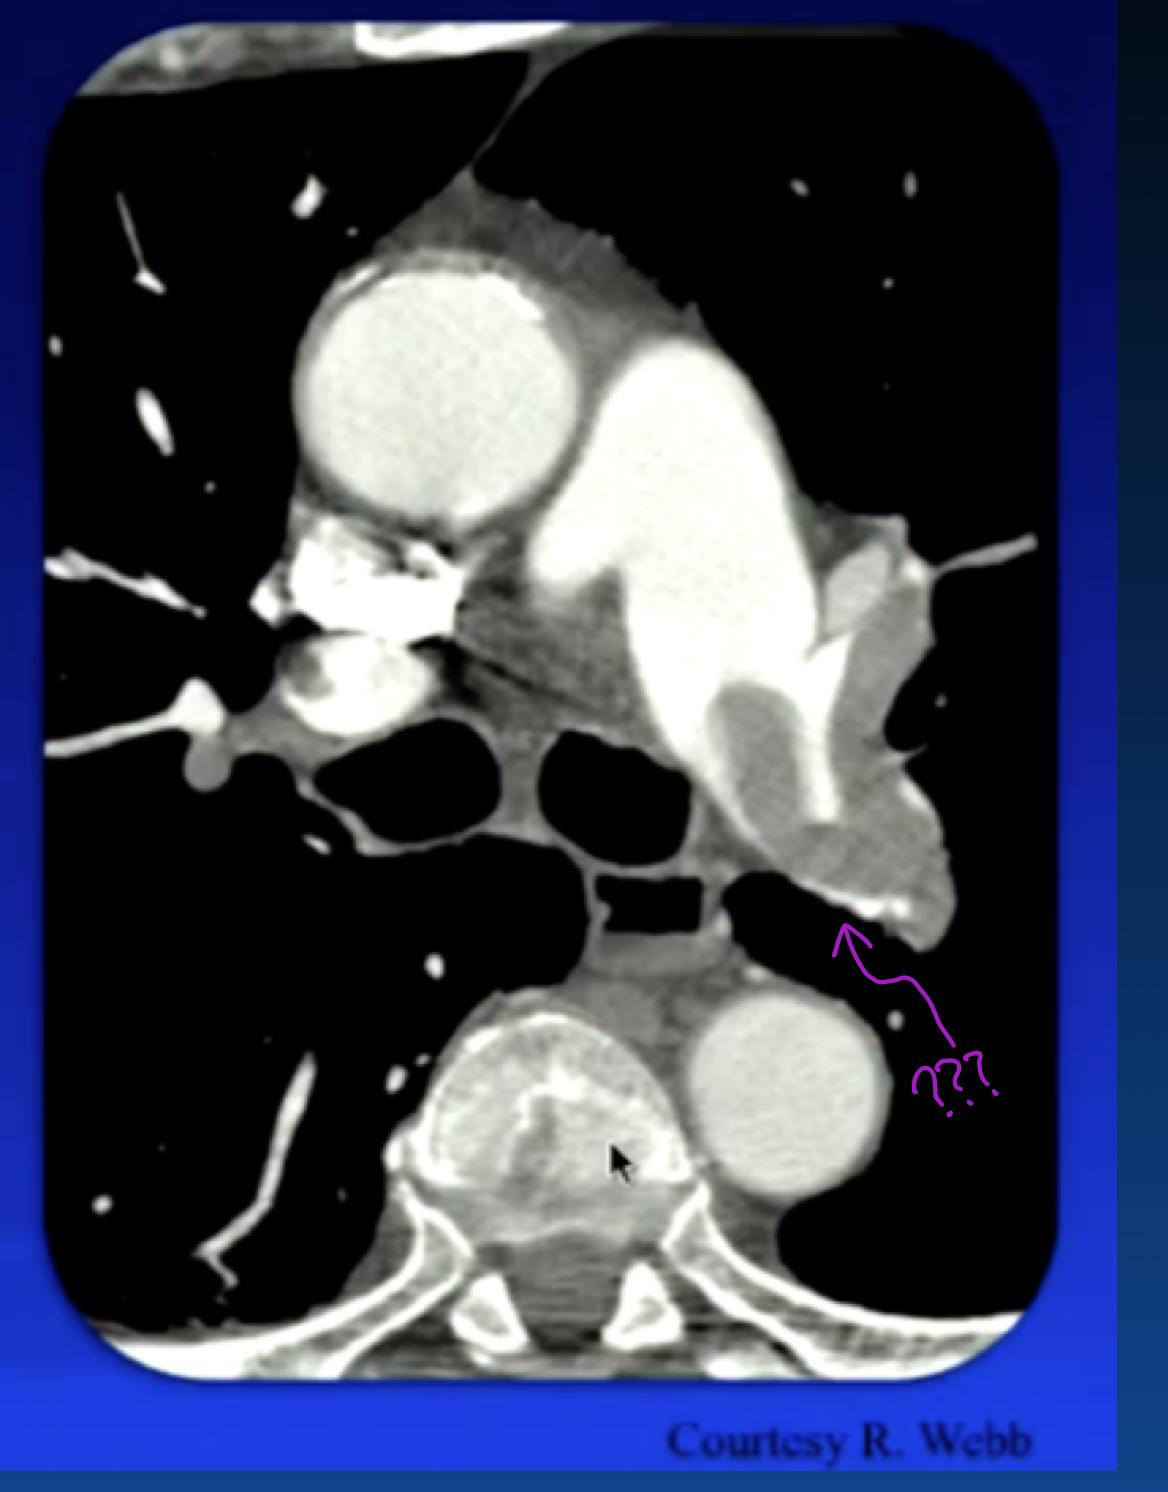

eccentric clot

What condition caused this? (the white arrow?)